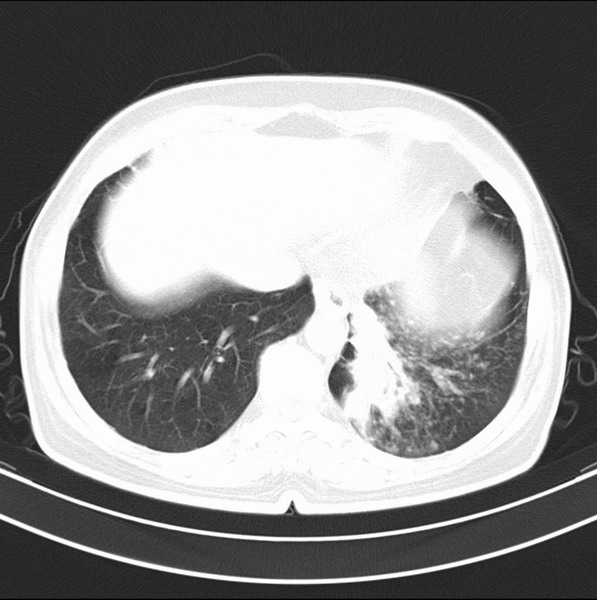

女、63

咳嗽、胸痛四个月

考虑左下肺中央型肺癌

支持左下中央型肺癌伴阻塞性炎症不张。

包绕左下肺基底段的不规则的软组织肿块,段支气管腔变形、狭窄及阻塞性炎症,病变区不规则强化,又是老年女性支持楼上看法。

典型病例:左下肺基底段中央型肺癌,相应支气管狭窄并阻塞性炎症